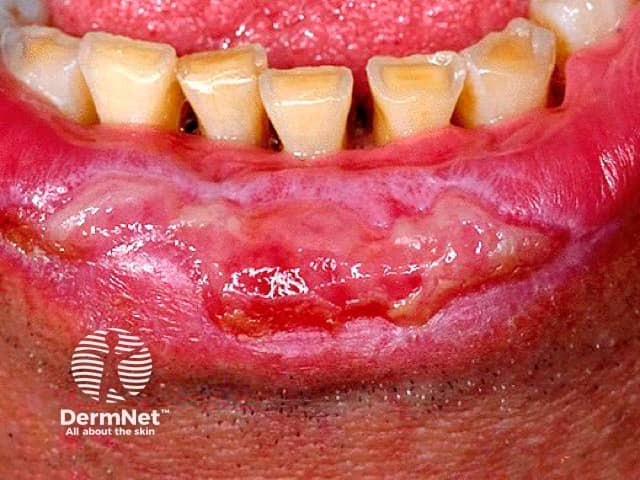

In the mouth, erosions and ulcers may be the only signs (ulcerative stomatitis). They may occur inside the cheeks, on the sides of the tongue, on the gums, or inside the lips. Unlike short-lasting aphthous ulcers, erosive lichen planus lesions are larger and more irregular, and they may persist for weeks or longer. It can be very painful to eat, resulting in weight loss, nutritional deficiencies and depression.

Other forms of oral lichen planus may also occur, including white lacy streaks and inflammation and peeling of the gums (desquamative gingivitis).

Erosive oral lichen planus